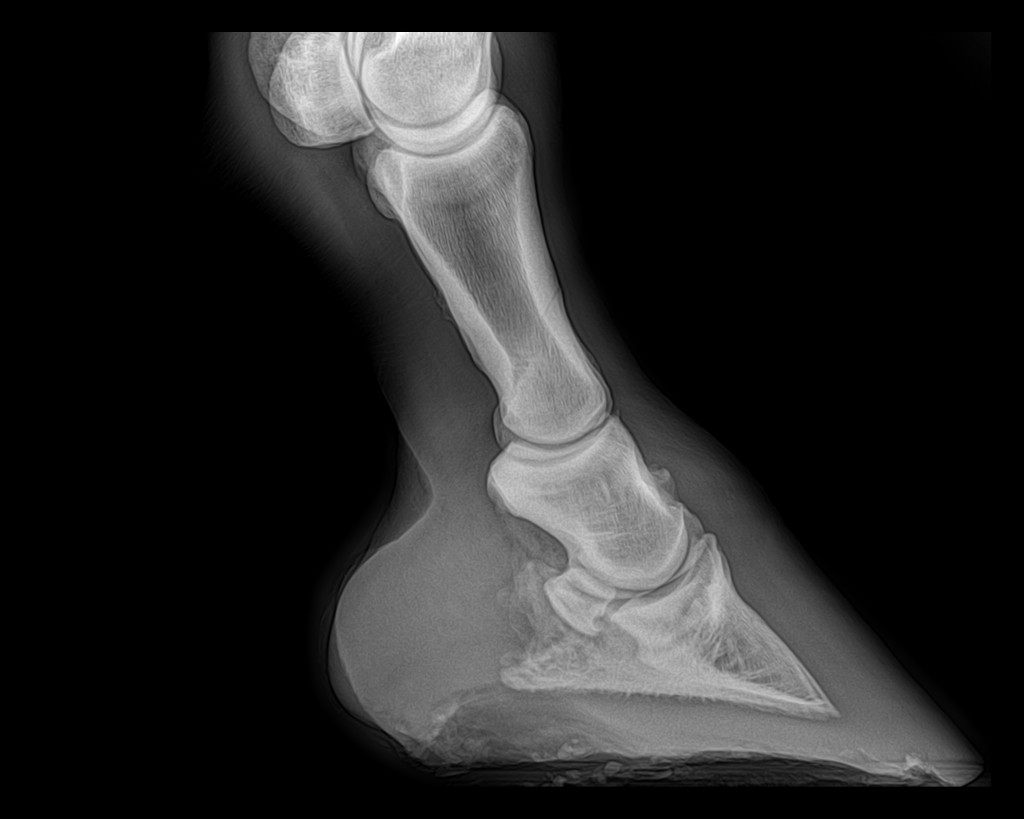

| Dire merci | juliie oui on aurait pu avoir pire, voici les derniers clichés radio du coup ( je sais qu'ils te font relativiser pour ton jaune ) AD ![]() ( On voit la petite pointe d'arthrose) AG ![]() (La on voit que la pointe d'arthrose est plus prononcée...Je sais si vous voyez, sinon j'entoure) Et là calcici...la calfifi...la Calcification ! ( Ça passe mieux sur un ton enjoué!) ![]() ![]() (Ce qui explique en grosse partie le côté trés sportif de ce journal ,heureusement qu'on bricole )erzebeth et takhan (mais je peux jamais t'identifier !!) Je vous prépare ça ( jsuis comme une folle ! J'adooooore les avants/aprés...sauf pr moi,là clairement ça va pas ds le bon sens ) |

| Dire merci | Oh punaise, la calcification fait pas rire ![]() Mais je prends volontiers ses sésamoïdes ![]() |